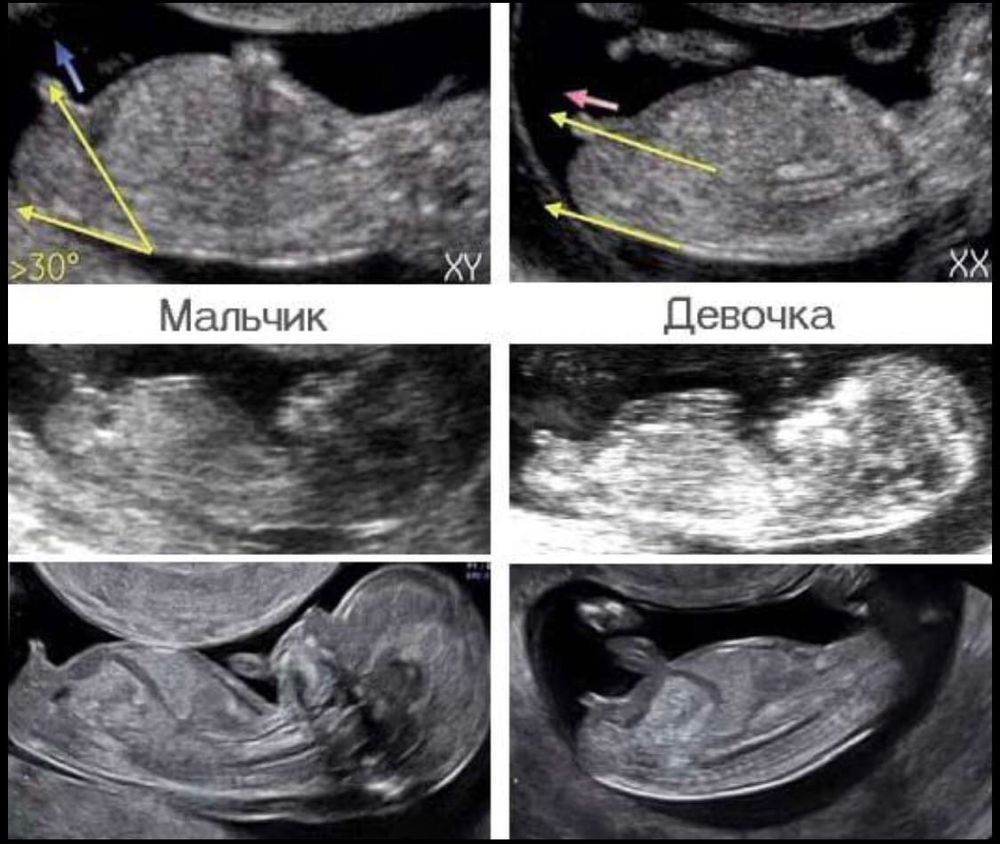

13 неделя

На первом скрининге тоже был мальчик. И на двух других промежуточных УЗИ тоже. Я была настроена на сына, и каково же было моё удивление, когда на втором скрининге точно и бесповоротно подтвердили девочку 😂

Мальчик или девочка Скоро гендер-пати🩷💙